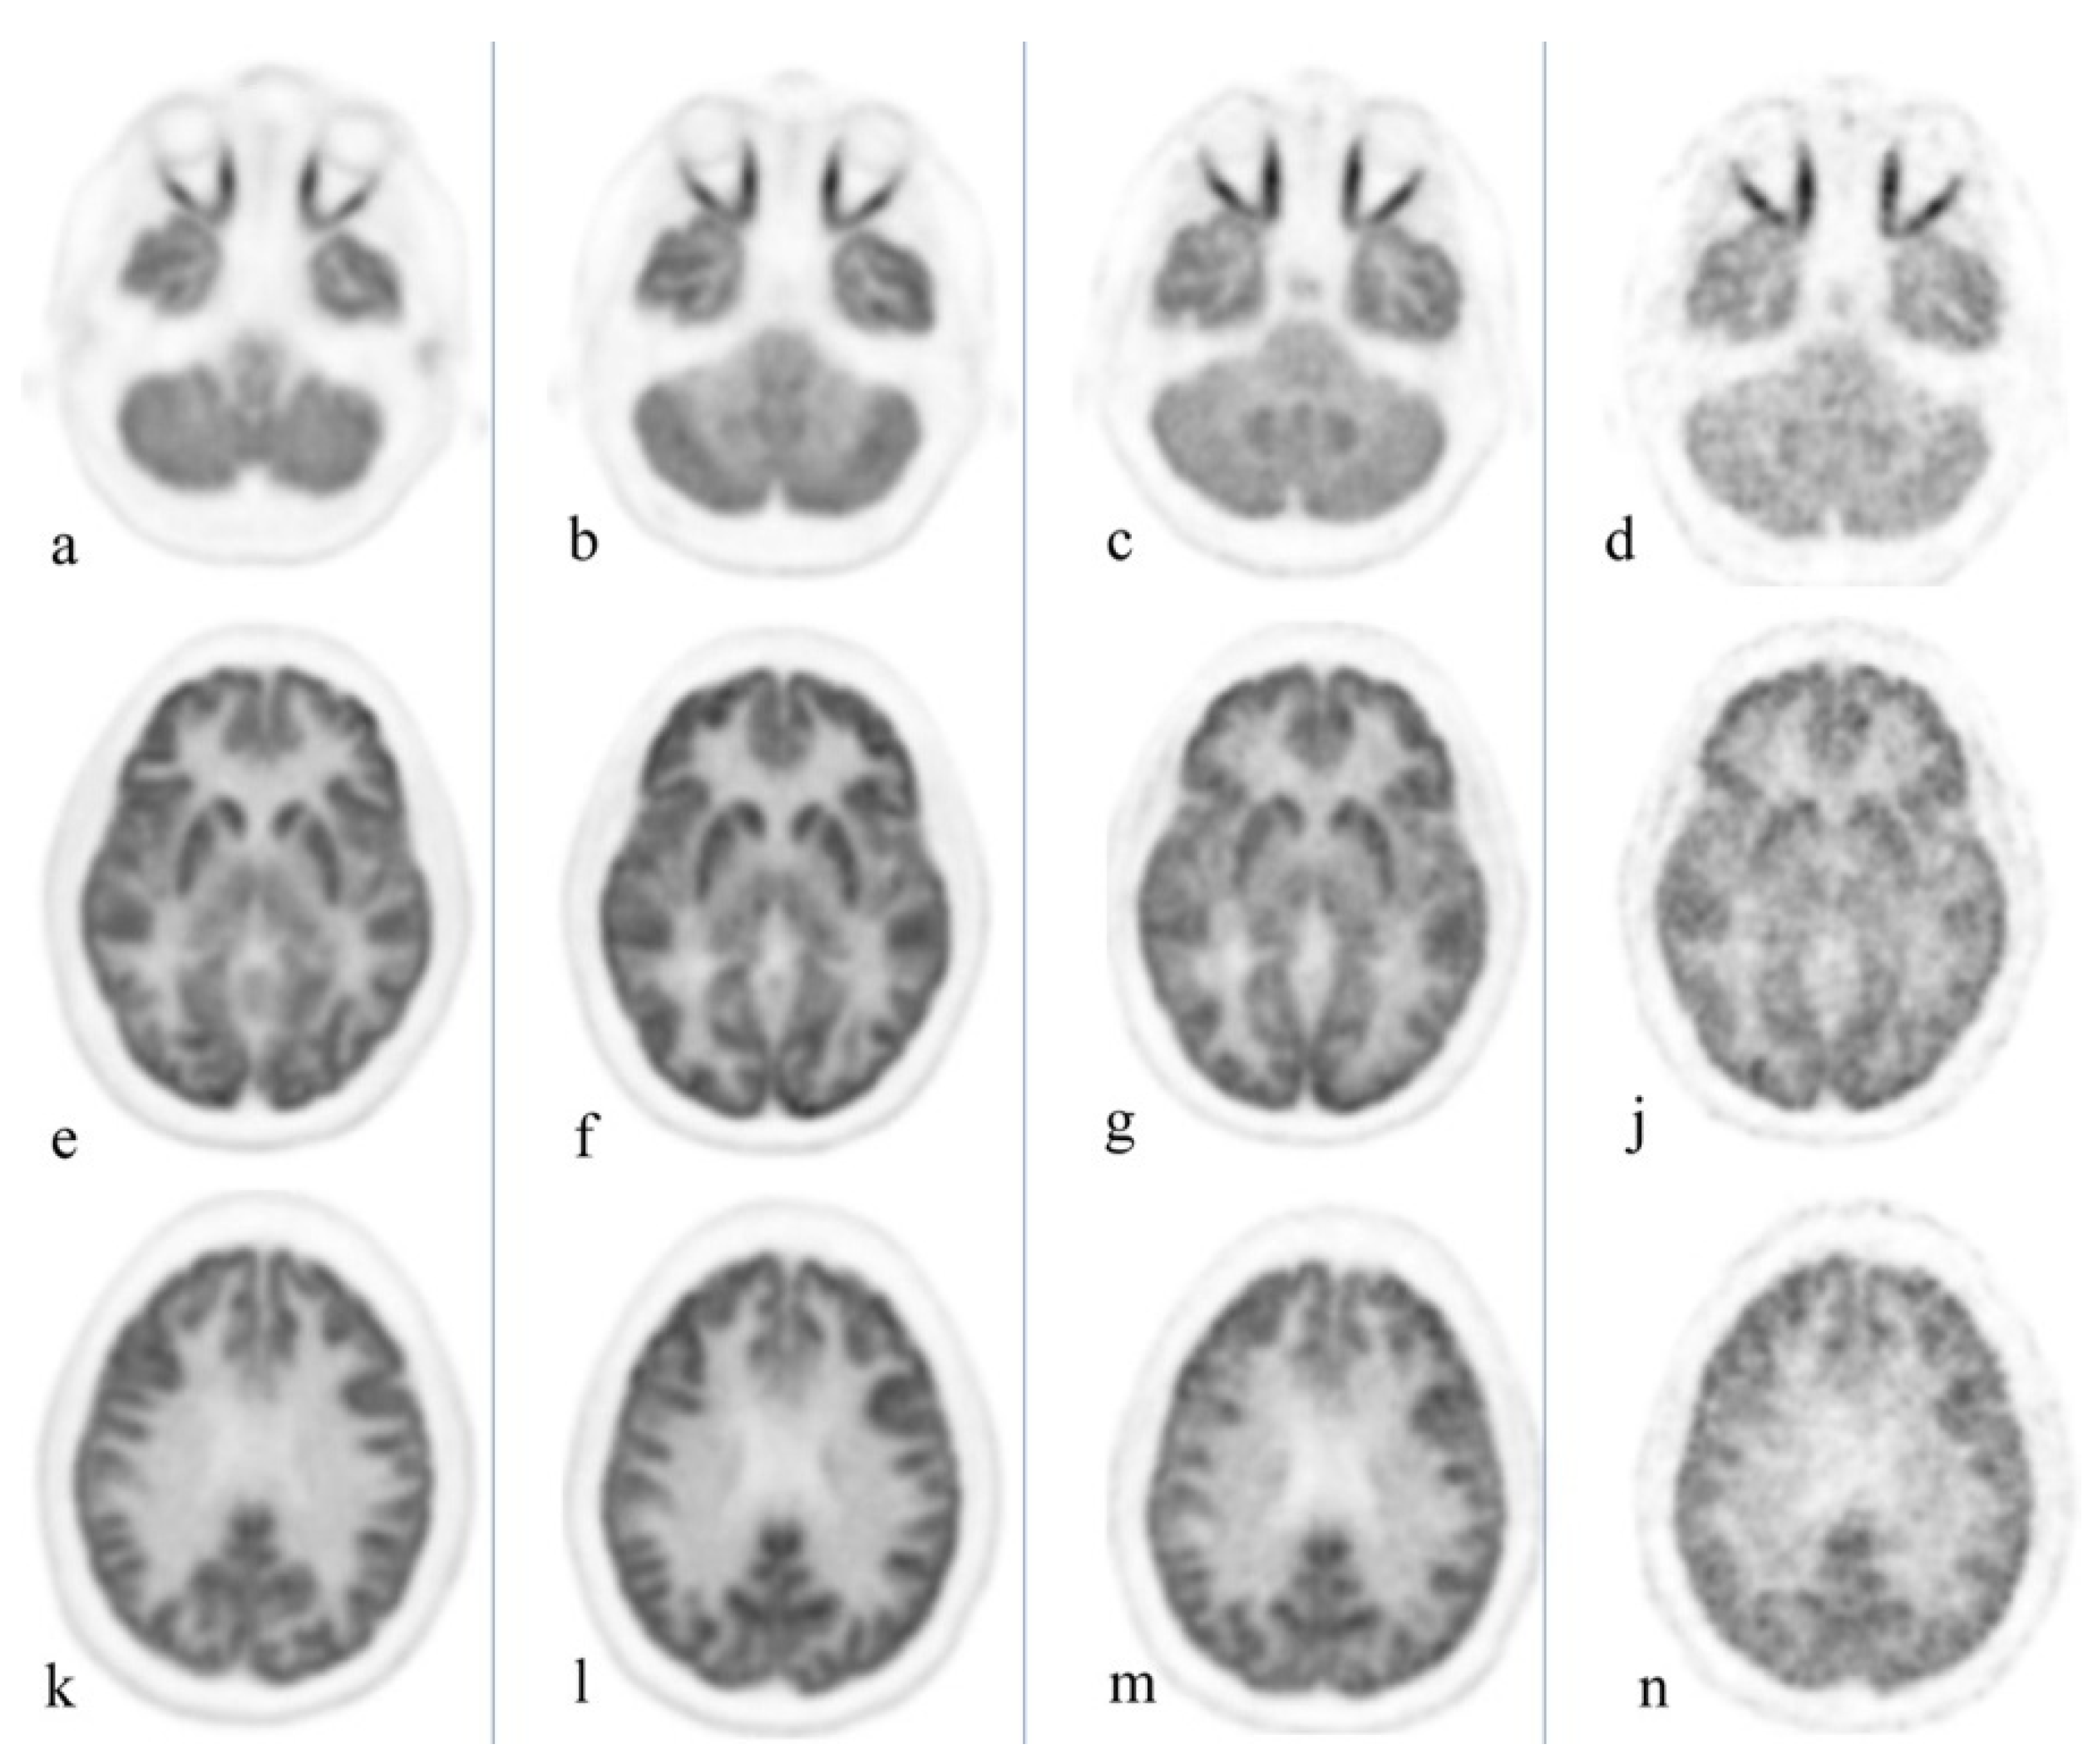

Delayed imaging further differentiates malignancy and inflammatory lesions even in FDG-avid organs such as the brain, as inflammatory changes are often characterized by early wash out [4]. Figure 3 exemplifies the substantially reduced activity associated with delayed imaging of the brain, thus ultimately enhancing detection of small/recurrent brain tumors. This differentiation between malignancy and infection/inflammation can also be achieved utilizing dual time point imaging as indicated by Zhuang et al. [20]. Moreover, this technique may potentially increase FDG sensitivity for tumor detection, thus providing the geographic tumor distribution and quantification of microscopic deposits throughout the body, information vital for ultra-staging and management decisions [21].

Figure 3.

Healthy volunteer, total body PET/CT 20-min acquisition at 40 min, 3 h, 6 h, and 9 h after administration of 10 mCi of 18F-FGD. Cuts were selected at the orbit level (a–d), basal ganglia (e–j), and upper aspect of the ventricles (k–n). Brain uptake slowly decreases over time; the increase in noise level starts to become clinically evident at 9 h. Reprinted with permission from Ref. [4]. Copyright 2020 Elsevier.